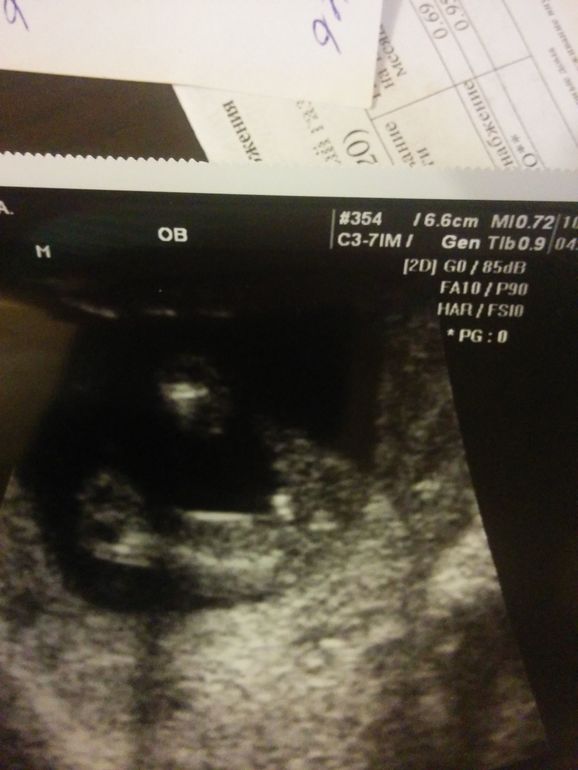

Пол малышаДевочки, всем спасибо за ответы. Пришла сейчас с узи. На двух ракурсах мальчика подтвердили! Я довольна ![]()

Начала сравнивать с нашим фото

Сказали, что больше похож на мальчика. А теперь я засомневалась.

Это не то, просто подсмазаось и что то торчит на фотке этой. Нам делали фотки, этот бугорок выше, в районе бедер

это точно не половой бугорок....он так низко просто не может быть. Ножка закрыла все самое интересное)))

Это не половой бугорок на вашем фото. Он выше гораздо и на фото его не видно из-за ножки. В 12 недель очень сложно подобрать хороший ракурс и разглядеть этот угол. А вот ближе к 14 он уже точно принимает градус, в зависимости от пола. И можно достаточно точно сказать. Нам узист эту информацию говорил. Пол он нам сказал в 14,1 недельку и не ошибся